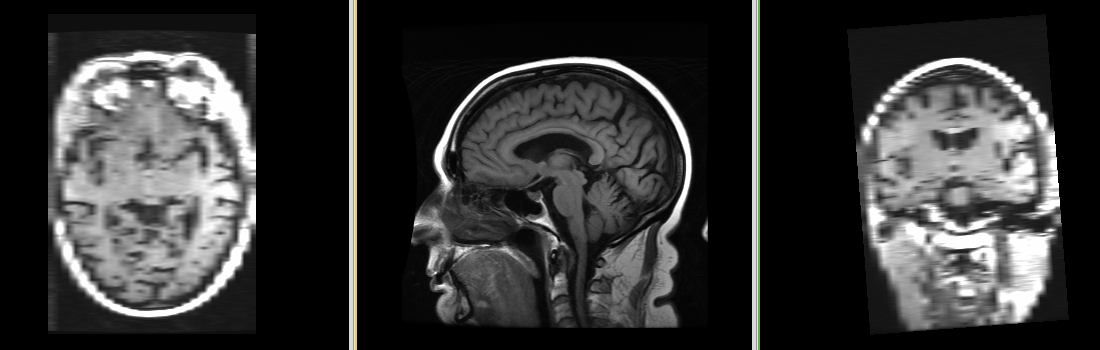

| Template (T1) | CSF | GM | WM |